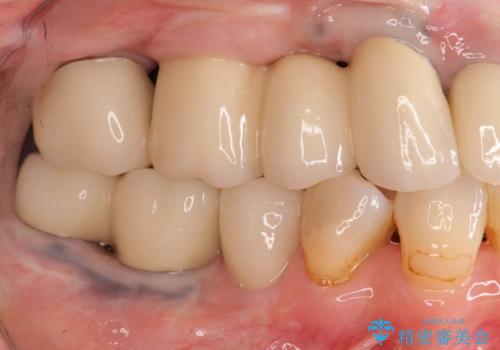

今後延々と治療を繰り返さないために、全ての銀歯を外し虫歯を丁寧に取り切り、根管治療を行い、残せない歯は抜去を行った上でインプラント治療を行っていくことで全体的な治療を計画していくこととなりました。

工程数が多かったため治療期間はかかりましたが、しっかりと安定した噛み合わせ、審美的な口腔内環境を達成することができ大変満足していただくことができました。